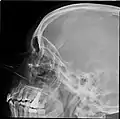

CT scans, radiographs (x-ray) and other illustrations

Paranasal sinuses radiograph (occipitofrontal)

Paranasal sinuses radiograph (occipitomental)

Paranasal sinuses radiograph (lateral)